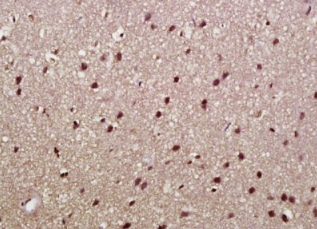

多聚甲醛固定,石蜡包埋(大鼠脑);用柠檬酸钠缓冲液(pH6.0)煮沸15min后获得抗原;用3%过氧化氢阻断内源过氧化物酶20分钟;阻断缓冲液(正常山羊血清)37℃30min;抗体(α-突触核蛋白)多克隆抗体在1:500下孵育。在4°C下过夜,然后用共轭二次进行20分钟的DAB染色。